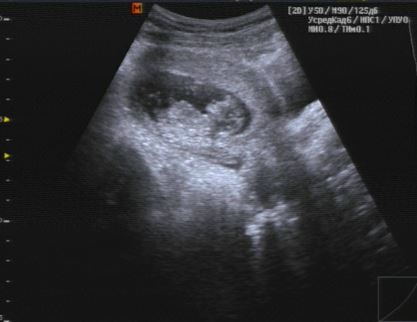

Встала на учет + 1 скрининг пройден (фото) ! 12 недель ровно

Изменения и болезни во время БНу вот, наконец-то я снова увидела свою бусинку!😍 Заряд эмоций теперь на весь день 🤗 Лялечка наша очень активна, шевелила и ручками, и ножками, так забавно за этим наблюдать! Столько волнения было перед осмотром, но врач почти сразу начал улыбаться и позвал мужа, чтоб показать ему. Тут то я и расслабилась.😁 Пол пока рано говорить, но сказали если мальчик - то через две недели уже будет заметно. А вообще точно сказать можно будет ближе к 20 недели.

По параметрам вроде все хорошо, КТР - 50мм, ЧС - 166 уд/мин, размер матки 109х88х88.

УЗИ смотрели только по животу, вагинально на этот раз датчик не вводили, все итак довольно хорошо было видно.